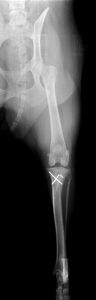

(左) 8ヶ月齢トイプードル 膝蓋骨内方脱臼グレード4 (右)一般的な膝蓋骨脱臼の治療手術に加え大腿骨の骨きりを実施した。(下動画) それぞれ術前の歩様と手術後4年の歩様